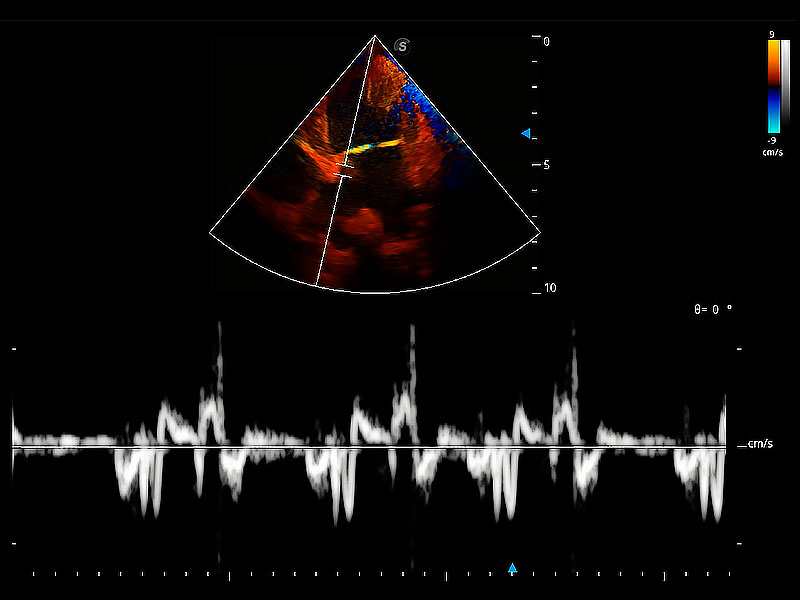

實(shí)時(shí)用顏色表示心肌組織運(yùn)動(dòng),觀察和定量組織的運(yùn)動(dòng)情況,對(duì)快速檢測(cè)與評(píng)估心肌的灌注和活性、電傳導(dǎo)及心肌收縮和舒張功能等均能提供重要的診斷信息。